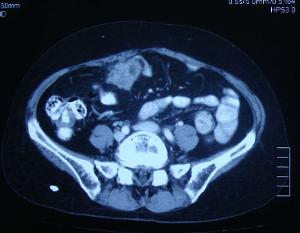

3 .CT:由于肠腔内存在气体和液体影响肿块的显示,对小肠诊断的帮组不大。

7.超声波:与CT一样对小肠肿瘤诊断意义不大,但对于巨大腔外肿瘤或确定有无腹膜后淋巴及肝转移有帮助。